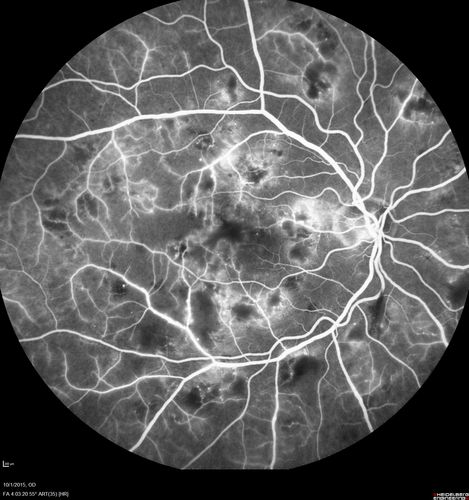

Hairy Cell Leukemia - Retinal Hemorrhage and twig Branch Vein Occlusion

79 year old man He has had hairy cell leukemia since 2002.  He is in remission.  His last blood tests were 9/2018.  He just moved down here and needs a new leukemia doctor.  His vision is fine.

VA OD: Dcc20/25

VA OS: Dcc20/25

IOP: TP: OD:12 OS:12